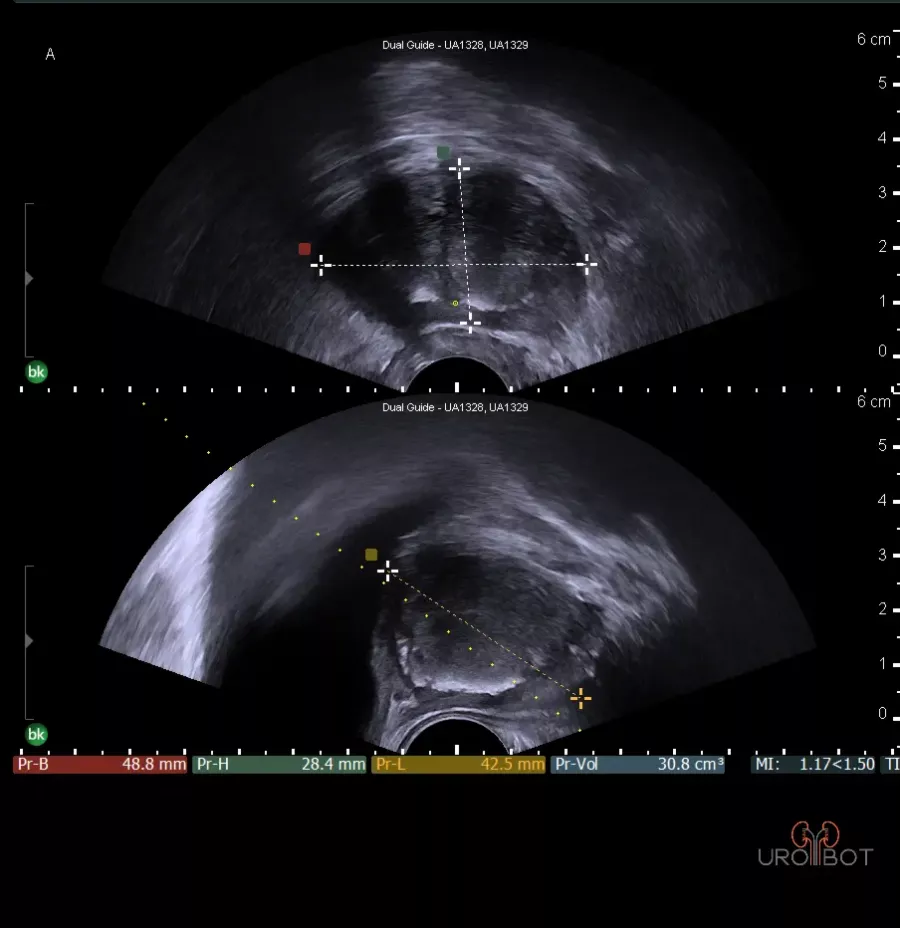

Es handelt sich bei dieser Untersuchung um eine Ultraschalluntersuchung der Prostata. Dafür wird ein stabförmiger Ultraschallkopf in den Enddarm des Patienten eingeführt. Die Untersuchung kann in Seitenlage oder in Steinschnittlage durchgeführt werden. Mit der speziellen Ultraschallsonde kann die Prostata gleichzeitig längst und quer dargestellt werden. Beurteilt werden:

- Form,

- Größe,

- Abgrenzbarkeit,

- die verschiedenen Zonen der Prostata,

- Homogenität,

- Samenblasen.

Das Video zeigt eine sonographische Untersuchung der Prostata, durchgeführt über eine sogenannte transrektale Ultraschallsonde.